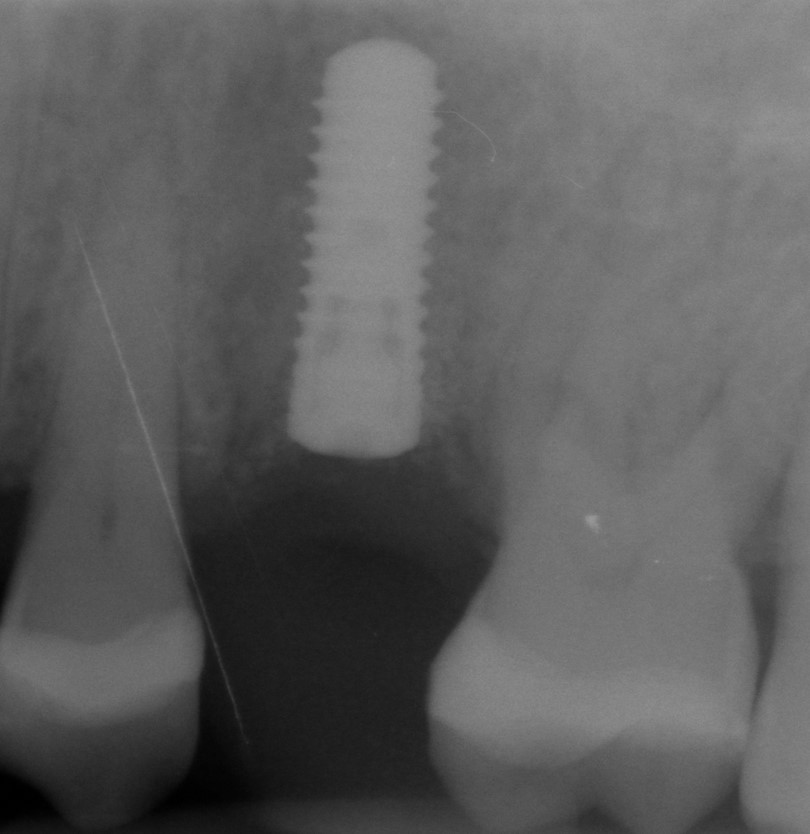

Implant insertion in atrophic alveolar ridge